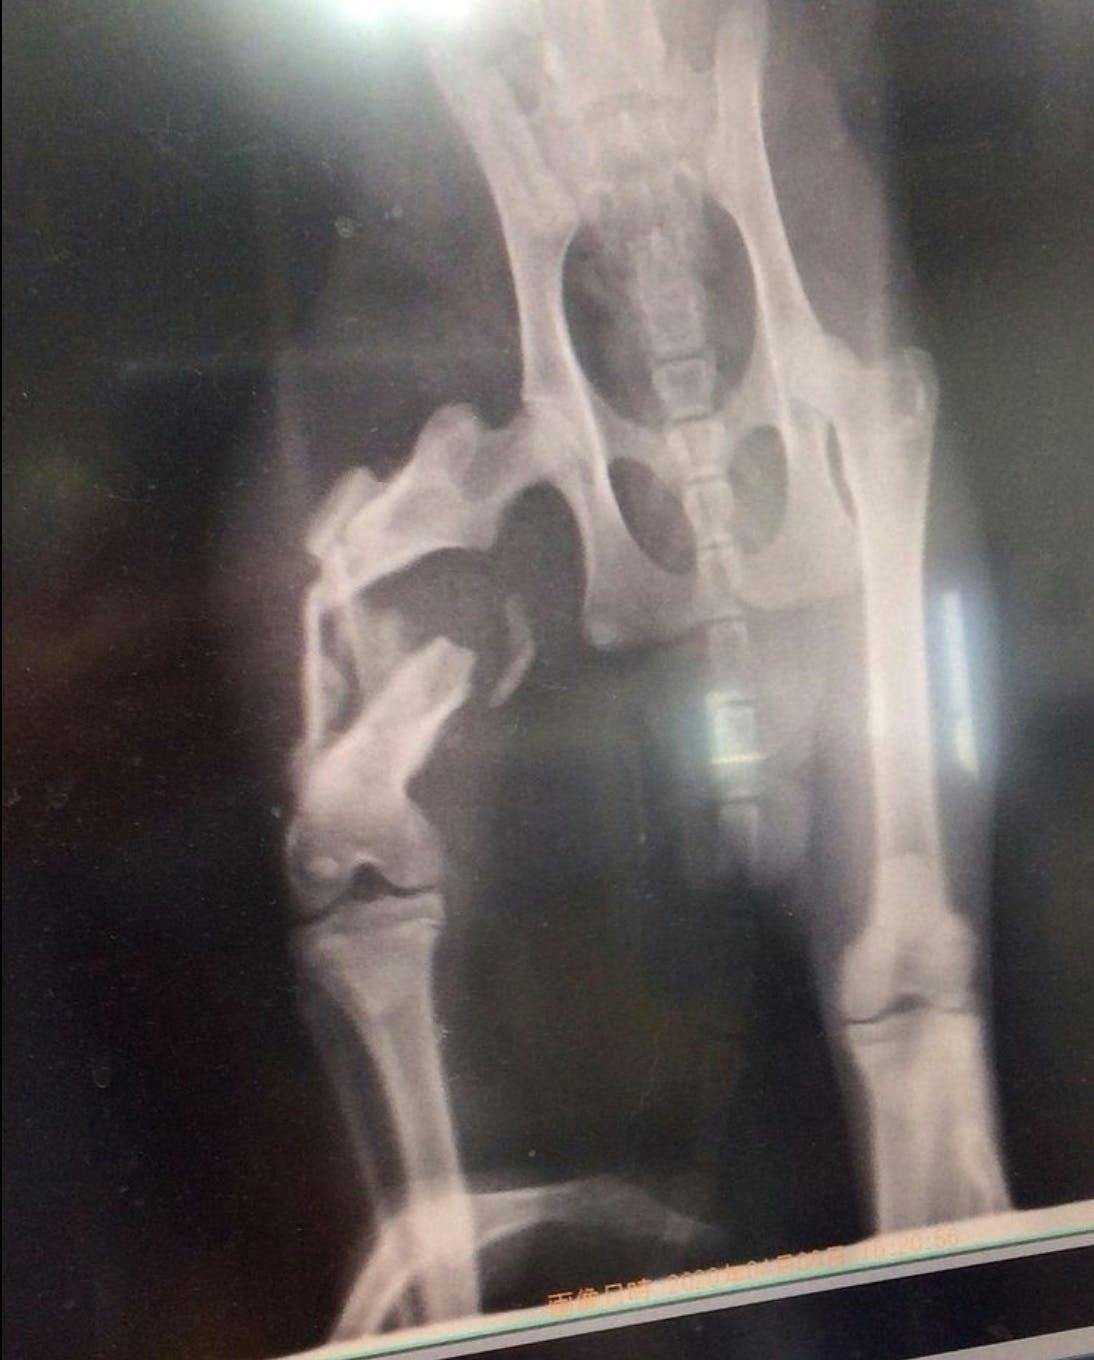

一朗くん

福岡県で足を引きずっている猫を発見し、その辺りの方に聞いたところ、

偶然にもそこでご飯をもらっていました。

その人が言うには、野良猫でご飯をあげていたが、車に轢かれ2週間ほど姿を消していたので、

死んだかなと思っていたそうです。そしたら、最近になってふらっと姿を見せたそうです。

人間が事故にあったら皆んな助けてくれるのに、猫の場合はほったらかしですか?

一人で2週間もの間 痛みに耐えていたんだね…

こんな辛い思いをした子を、放ったらかしにして帰ることが出来ず、保護させてくださいとお願いしました。

今では、本当に骨折してたの??と思うくらい走り回っています。